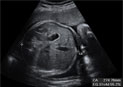

Ecografía del tercer trimestre: Doppler del cordón umbilical

La ecografía Doppler en el tercer trimestre de embarazo permite conocer cómo es la flujo sanguíneo en el cordón umbilical. Si resulta normal quiere decir que el feto recibe la cantidad de oxígeno necesario para su correcto desarrollo.

Ecografía Doppler normal del cordón umbilical

La ecografía Doppler nos ayuda a valorar si el estado de salud fetal es adecuado.